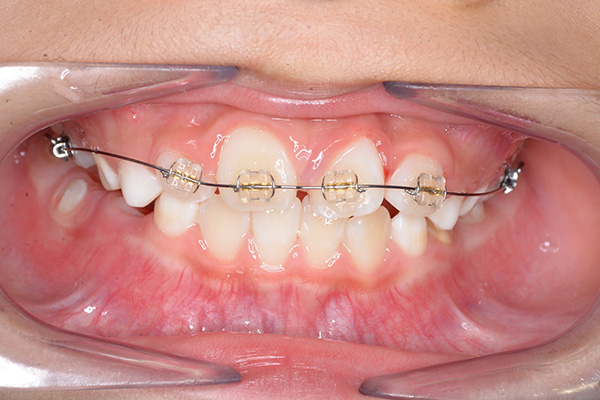

| 主訴 | 上顎前歯のでこぼこ | 診断名 | アングルⅡ級叢生症例 | ||||

|---|---|---|---|---|---|---|---|

| 初診時年齢 | 6歳9ヵ月 | 性別 | 男 | 動的治療期間 | 6ヵ月 | ||

| 使用装置 | 0.018" × 0.025" standard edgewise | ||||||

| 既往歴として上顎正中過剰歯(2本)は抜去済み。その影響で上顎右側中切歯は捻転して萌出しており、下顎右側中切歯と早期接触が認められたため2x4(上顎のみブラケット装着)にて前歯部の改善を行った。現在は永久歯列完成まで経過観察を行い、希望があれば口元の突出感を改善するために本格矯正治療を行うことにしている。 | |

| 批評・予后 | 早期治療によって前歯部の咬合干渉は回避され、その後の永久歯への交換は順調である。 |